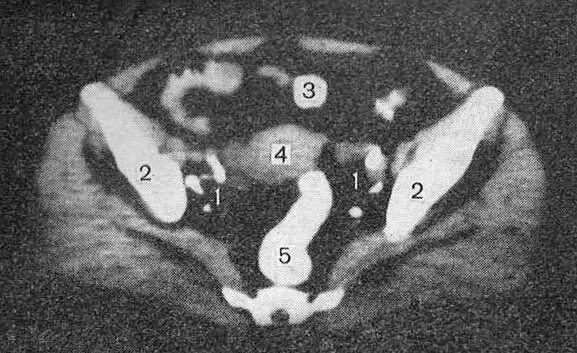

Метастазы в матке